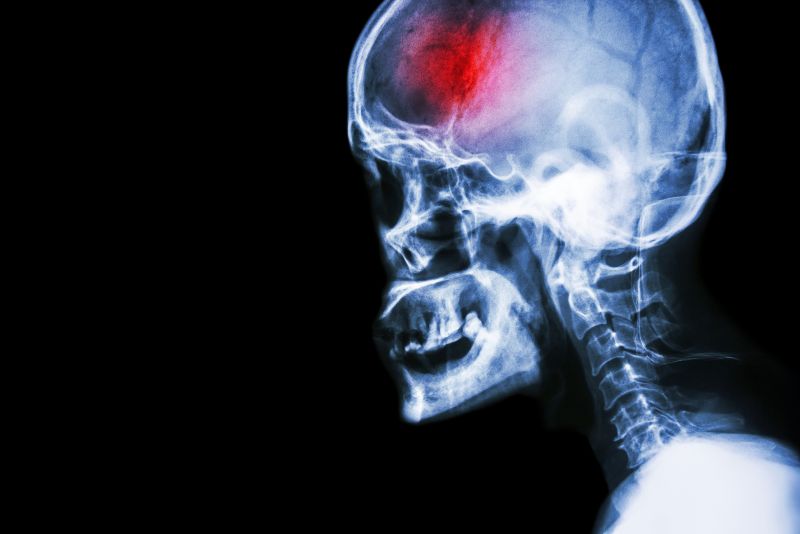

Head X-ray

Head X-rayA stroke is a serious medical emergency that requires immediate action in order to achieve the best eventual outcomes. Early medical intervention, as well as early, consistent and ongoing rehabilitation will positively affect your long term capabilities.  Physical therapy services at FYZICAL Tifton can assist you to recover from your stroke and regain your maximum potential.